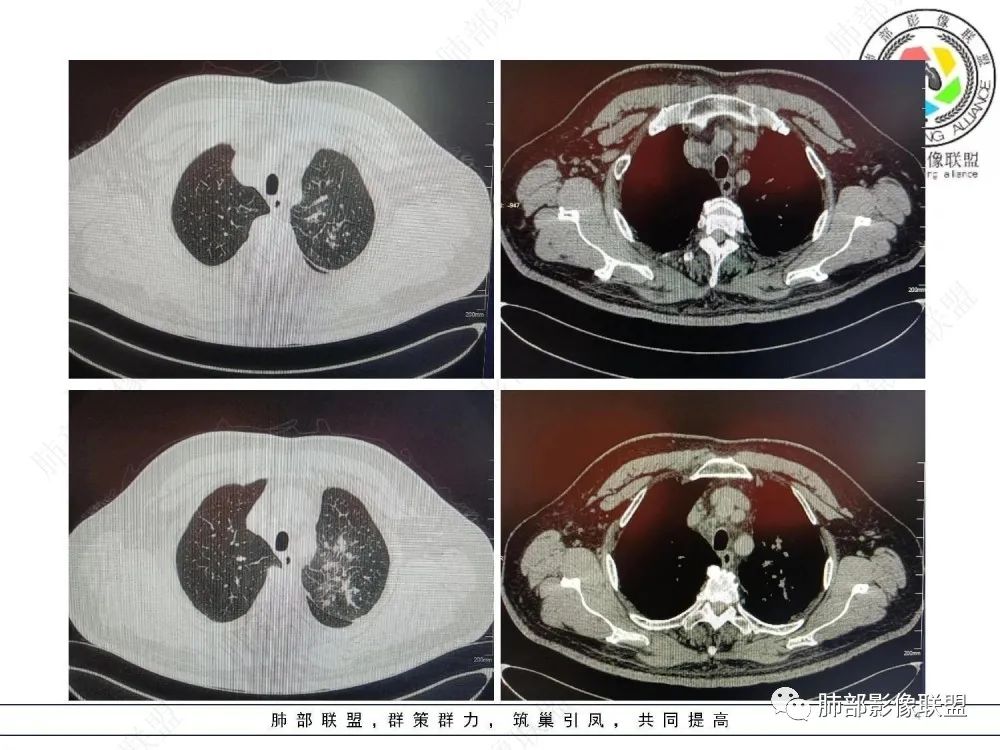

三、影像表现:左肺上叶多发片状高密度影,散在,边缘模糊,支气管壁稍增厚,中轴间质、小叶间隔增厚、有结节感,左肺上叶前段病灶可见胸膜增厚,部分小支气管不能分辨;右肺上叶后段混合磨玻璃结节,边界清,邻近胸膜凹陷;纵膈淋巴结肿大;心包增厚;左侧少量胸水。此外,扫及右侧胸腔内甲状腺肿;左侧肩胛骨旁肌群内脂肪瘤。

四、综合分析:老年男性,以咳嗽咳痰为主要临床表现,无发热,白细胞正常,影像表现为左肺上叶片影,前段结节影、胸膜增厚、部分小支气管不能分辨。左肺上叶中轴间质增厚、小叶间隔增厚、结节感,肺门纵隔见肿大淋巴结,尽管肺部病病灶边缘特征不典型,但高度疑及癌性淋巴管炎这一“次生灾害”却具有相当重要提示意义,而肺癌中最常伴癌淋的就包括腺癌。右肺上叶后段混合磨玻璃结节,边界清楚,张力明显,具有一定特征性,高度指向浸润性腺癌。这对于左肺病灶具有一定程度“助攻”效应。总体而言,本例左肺病灶的诊断关键点在于判断出癌性淋巴管炎。癌性淋巴管炎的结节在外围间质多见,小叶间隔可呈串珠状、结节状增厚,由于出血及水肿,小叶间隔增厚较明显,或呈不规则增厚。有的肺小叶呈多角状阵列。常合并胸水。